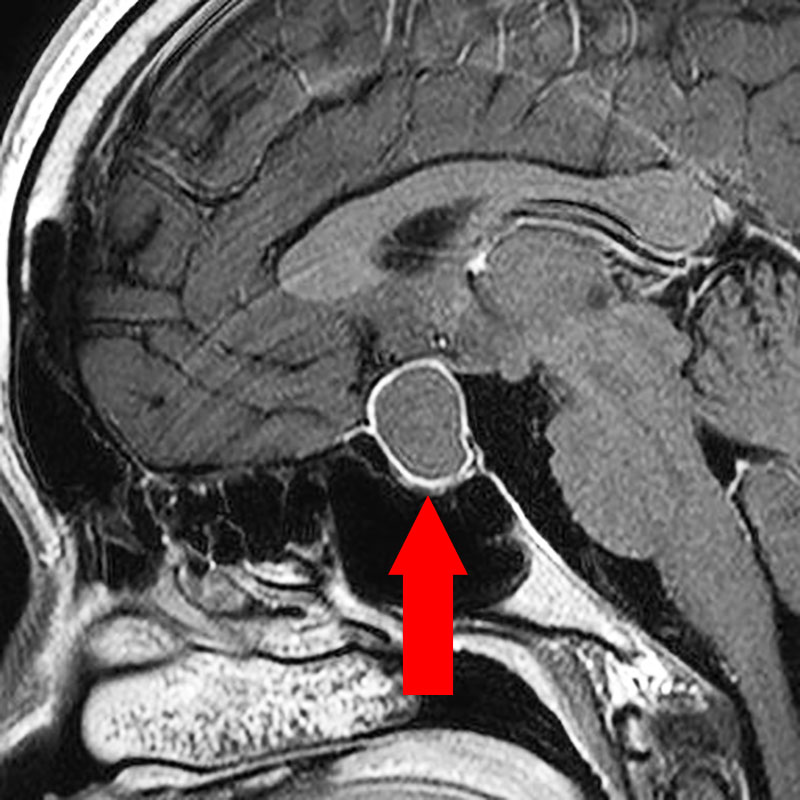

断層撮影

手術前1

手術前2